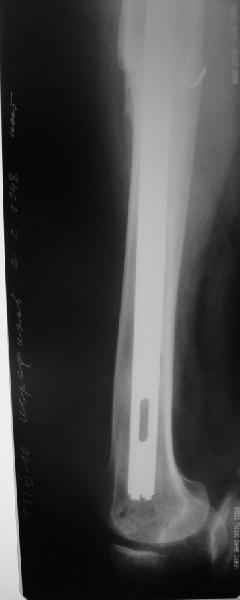

[Ortho] Перипротезный перелом

Пациента удалось осмотреть недавно. Достигнутый результат сохраняется.

Перелом бедра сросся. Конечность опорная и безболезненная, ходит без

трости. Ножка, похоже, реинтегрировалась, как и надеялись.

Снимки и фото в приложении.

Надо ли что-то делать дальше, как полагаете? Убрать винты? Убрать

"удлинитель ножки"? Или оставить все, как есть? Спасибо заранее.